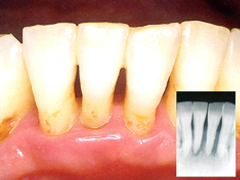

重度歯周病

状態 : 歯ぐきが下がり、骨も半分以上溶けている状態で歯根が見えている状態です。

症状 : 歯がぐらぐらし、歯が抜けることが多いです。食べものを咬むことも難しくなります。

治療法 : 多くの場合、抜歯することになります。